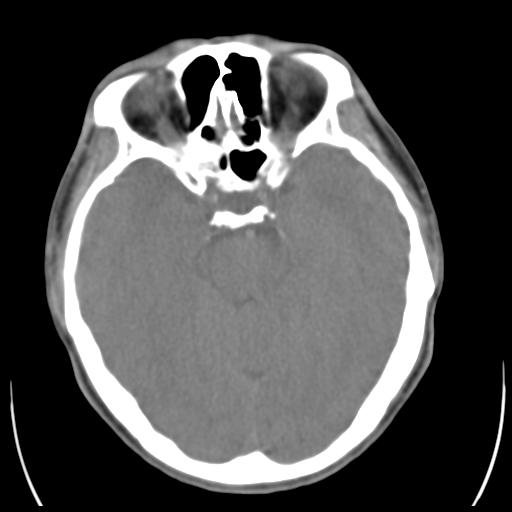

35m 鼻子时不时流血,头及右侧面部痛,颈部淋巴结未见明显大

骨窗

考虑鼻咽癌侵犯颅底并突入右侧鼻腔;双侧中耳乳突炎。

蝶窦,后组筛窦及鼻咽部团块状软组织影,骨壁破坏,病变较广泛。考虑恶性肉芽肿。建议活检。

颅底骨质明显破坏 支持鼻咽癌 但病灶的边缘毛糙 不能除外炎性

蝶窦,后组筛窦及鼻咽部团块状软组织影,骨壁破坏,病变较广泛。考虑炎性肉芽肿性病变可能。建议活检。